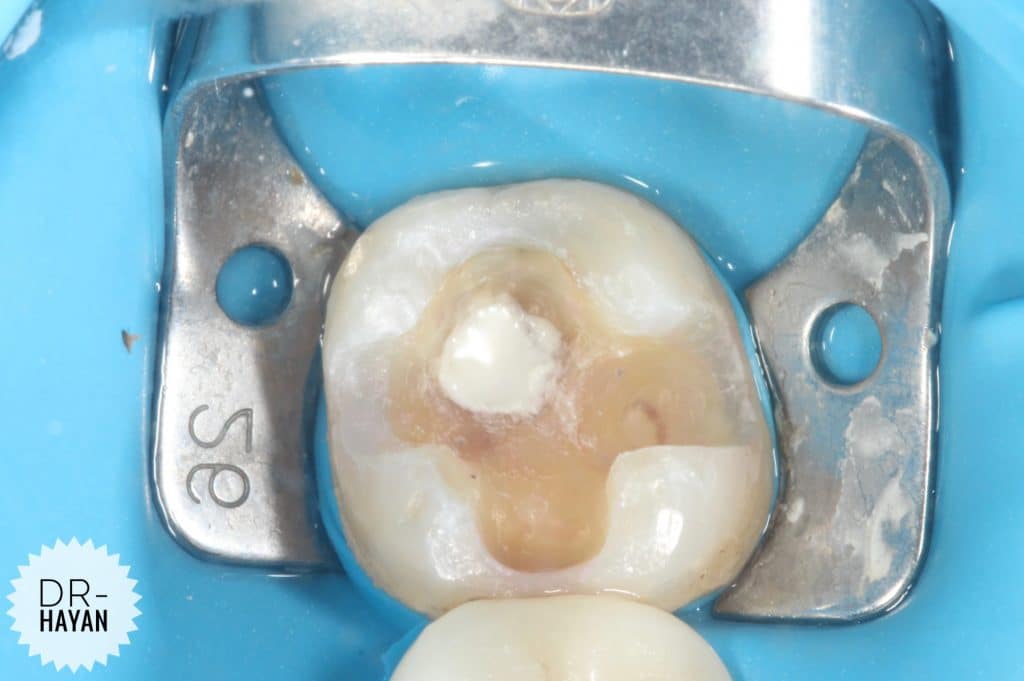

After remove the amalgam

As usual , recurrent caries under it

Remove the caries & finishing the margin

CDD

Although caries indicating dyes are not highly specific, the intensity of the stain can be utilized to selectively remove stained areas. In general, areas with a darker, more intense stain tend to have a greater degree of demineralization and carious bacteria. Areas with a lighter stain may not be affected and can be left in place.

Some infected dentine

you can note the different under magnification , specifically around the discoloration dentine